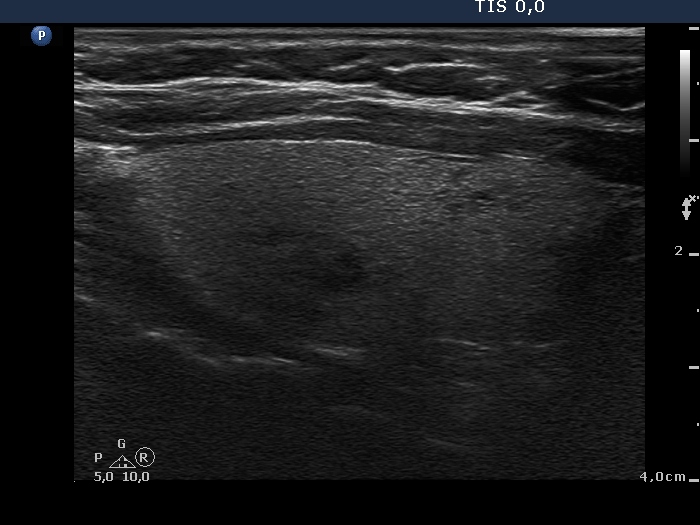

Ultrasonography. There were two nodules in the left lobe. The upper one was echonormal while the lower hypoechogenic one contained microcalcification and a cotton-like larger hyperechogenic patch and presented an irregular shape and an intranodular vascularity.